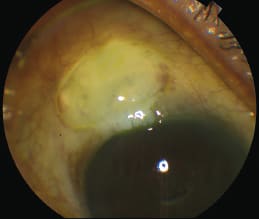

Figure 1. The patient’s right eye. Visual acuity was 20/25 uncorrected both eyes and IOP was 13 both eyes. Right eye on timolol qam and left eye on timolol, brimonidine, dorzolamide, pilocarpine and travaprost. The patient’s IOP decreased to 7 mm Hg on postoperative day one, but had risen to 17 mm Hg one month later despite releasing sutures and one 5-FU injection. He developed a high myopic and astigmatic shift after the 5-FU that later resolved, but I decided not to repeat the injection. In July 2010, IOP was 21 mm Hg. We performed bleb needling in the minor procedure room with 0.2 ml injection of 0.4 mg/ml MMC. IOP was 5 mm Hg immediately after. The IOP stayed in the single digits for one month but it was 19 mm Hg seven weeks later. I injected 0.2 ml of 0.2 mg/ml MMC in the office one more time and continued prednisolone acetate 1% drops and massage for four more months on slow taper. IOP stabilized between 12 and 13 mm Hg on timolol QAM only over the last 30 months. I last saw him in mid-September of this year when we obtained photos (Figure 1). |